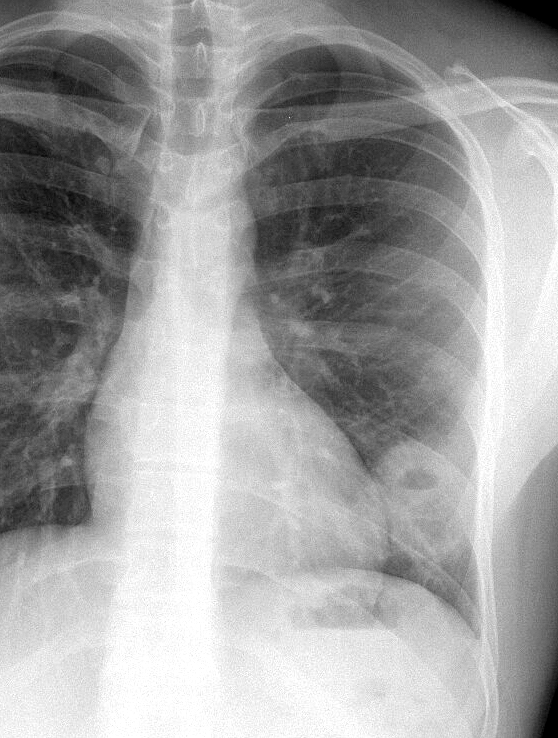

Case 18 Cavitating pneum/Abscess PA